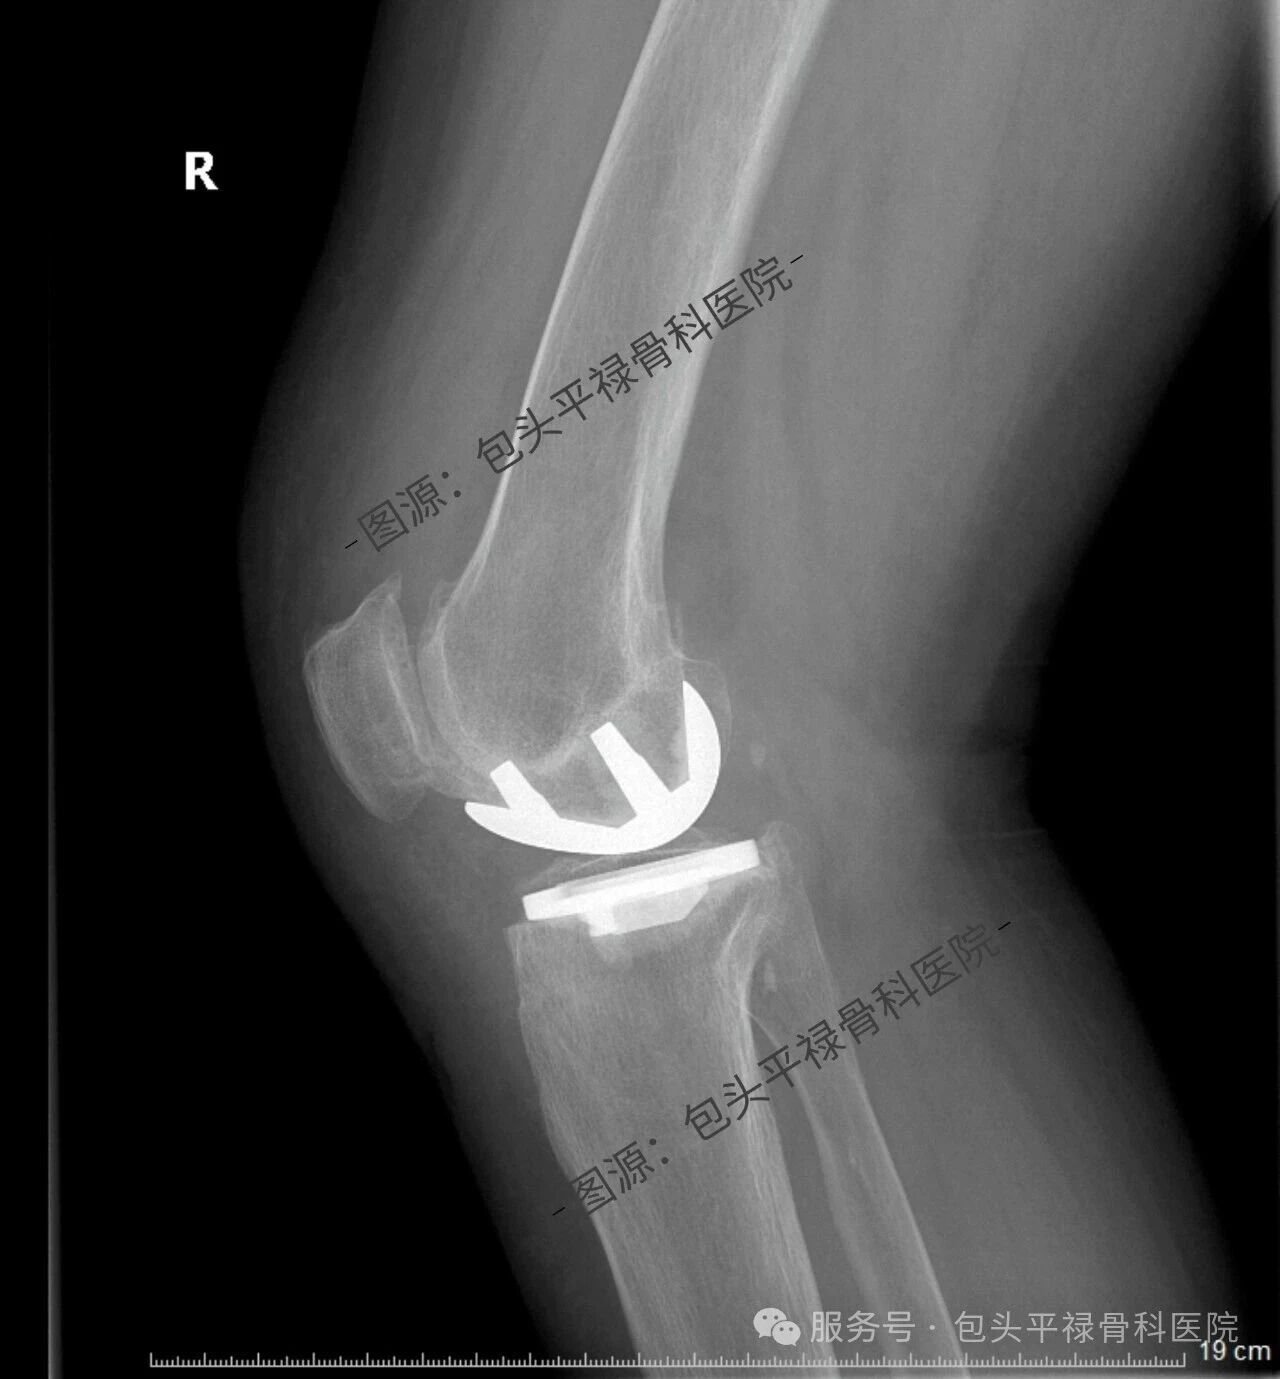

其实,现代医疗技术日趋精准,如果患者的关节炎只局限于膝关节的一个部分(单侧间室),那么TA很可能适合一种更为精准、创伤更小的手术——膝关节单髁置换术。

单髁置换:精准的“局部翻新”

膝关节单髁置换术相当于“局部翻新”,就是只置换“坏掉房间”的磨损表面,仅将受损的软骨和部分骨质去除,替换为人工假体,而完好的软骨、交叉韧带及其他结构都得以最大程度的保留。